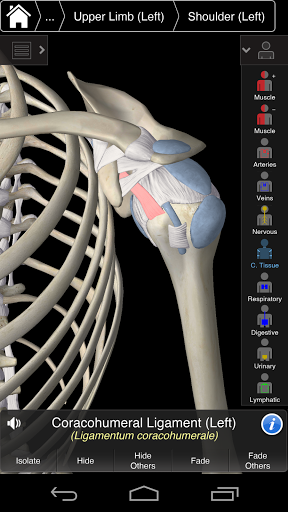

Essential Anatomy 3 representa lo último en tecnología 3D innovadora y diseño innovador. Un motor de gráficos 3D de vanguardia, creado a medida por 3D4Medical desde cero, alimenta un modelo anatómico altamente detallado y ofrece gráficos de calidad excepcional que ningún otro competidor puede lograr.

La aplicación representa un enfoque único para el aprendizaje de la anatomía general. Los gráficos no tienen paralelo y hacen que el aprendizaje, a través del uso de contenido informativo y características innovadoras, sea una experiencia rica e interesante.

Essential Anatomy 3 es receptivo, visualmente impactante y sin esfuerzo. La aplicación es totalmente en 3D, lo que significa que puedes ver cualquier estructura anatómica de forma aislada y desde cualquier ángulo.

La funcionalidad inteligente que se encuentra dentro de la aplicación permite al usuario eliminar capas de músculo a través de la herramienta 'bisturí'. Esta aplicación ofrece a los usuarios la posibilidad de activar / desactivar sistemas sin la necesidad de anular la selección de estructuras individuales o mezclarse en una multitud de pestañas regionales predefinidas, como otras aplicaciones.

---- Más de 4,000 estructuras anatómicas altamente detalladas

---- Nomenclatura latina para cada estructura anatómica